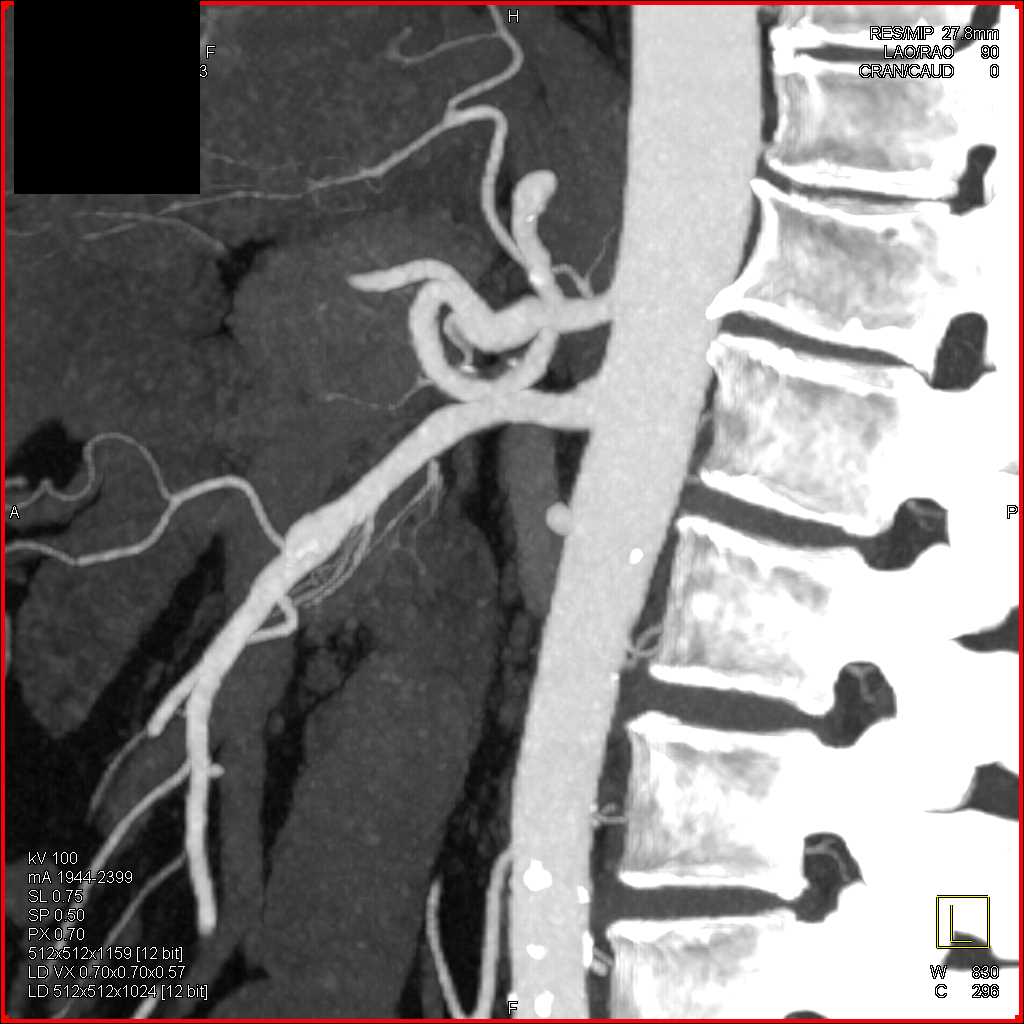

SMA Stenosis